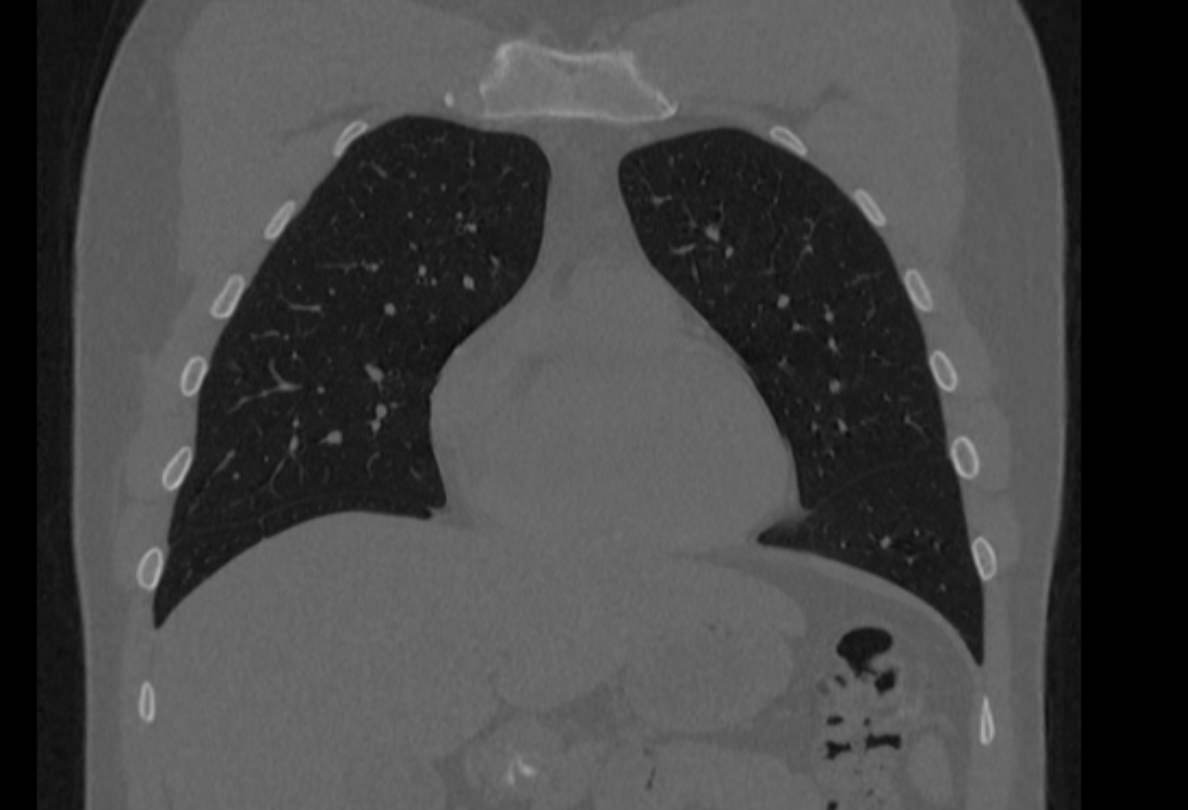

Мультиспиральная компьютерная томография грудины входит в протокол обследования КТ органов грудной клетки и является прицельным исследованием области грудины и грудино-реберных сочленений.

Мультиспиральная компьютерная томография является наиболее информативным методом диагностики патологии грудины. Метод основан на применении ионизирующего излучения и получения изображений внутренних органов за счет различной способности тканей поглощать рентгеновские лучи.

В диагностических центрах «Доступная медицина» сканирование области грудины выполняется на новейших мультиспиральных компьютерных томографах экспертного класса TOSHIBA AQUILION. Современное оснащение аппаратов позволяет проводить одномоментно множество тончайших срезов толщиной от 0,5 мм за несколько секунд. Скоростное сканирование обеспечивает минимальную дозу рентгеновского облучения для пациента. При этом сверхчувствительные детекторы и цифровые приложения, установленные в томографах, позволяют получать детальные снимки и цифровые 3D-реконструкции высокого качества для быстрой и точной диагностики.

При проведении мультиспиральной компьютерной томографии на снимках и трехмерных изображениях хорошо видны костные структуры грудины, передней поверхности ребер, грудино-ключичных и грудино-реберных сочленений. Также можно увидеть строение и патологические процессы в органах средостения: трахеи, пищевода, лимфатических узлов средостения, вилочковой железы, загрудинно расположенной щитовидной железы, грудной аорты, сердца и перикарда, жировой клетчатки средостения.